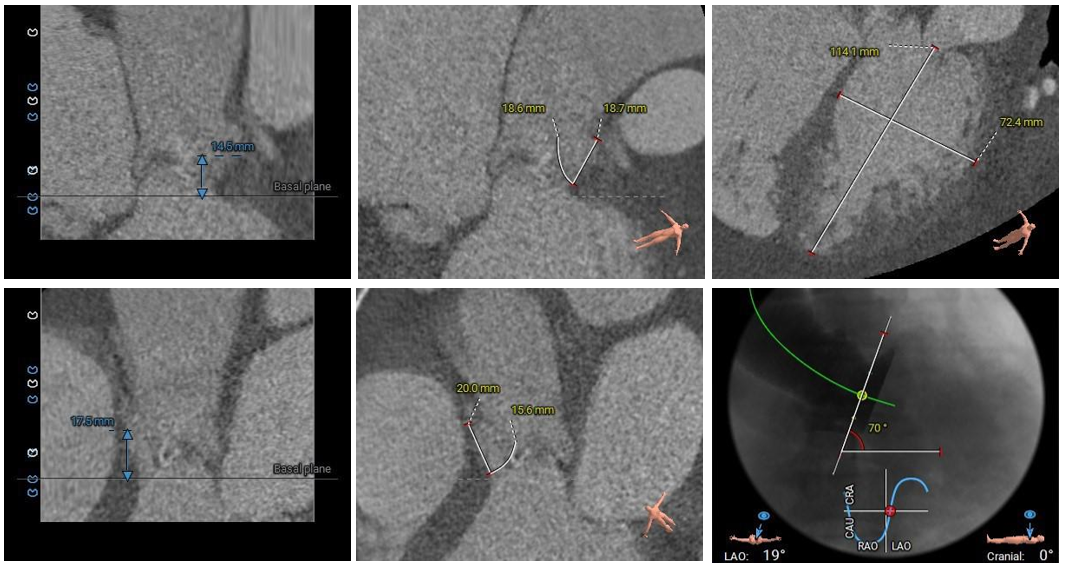

术前CT评估

Type0型二叶式主动脉瓣,左右冠共窦,瓣叶轻度增厚伴轻度钙化,钙化主要分布于两窦交界处前缘;LVOT呈敞口状形态;

冠脉开口高度尚可,切线位未见左右冠瓣叶冗长;

瓦氏窦、窦管交界内径尚可,升主动脉瘤样扩张;

左室腔内径明显偏大,心室壁偏薄;

主动脉瓣环与水平面夹角为70° ,主动脉弓部夹角及弓距尚可;升主动脉可见扭曲;

主动脉根部测量

瓣上结构测量

冠脉阻挡风险、左室大小及横位心评估